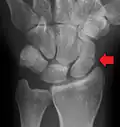

Fracture of the tubercle of the scaphoid bone of the wrist

Scaphoid fractures are often diagnosed using plain radiographs and multiple views are obtained as standard.[9] However, not all fractures are apparent initially.[7] In 1/4 of cases, the clinical examination suggests a fracture, but the X-ray does not show it, even though there is indeed a fracture.[10] Therefore, people with tenderness over the scaphoid (those who exhibit pain to pressure in the anatomic snuff box) are often splinted in a thumb spica for 7–10 days at which point a second set of X-rays is taken.[7] If a minimally displaced fracture was present initially, healing will now be apparent. Even then a fracture may not be apparent. A CT Scan can then be used to evaluate the scaphoid with greater resolution. The use of MRI, if available, is preferred over CT and can give one an immediate diagnosis.[11] Bone scintigraphy is also an effective method for diagnosis fracture which do not appear on Xray.[12]